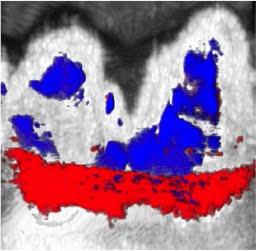

Squid ink naturally contains melanin nanoparticles, which absorb light. During the oral rinse, the melanin nanoparticles get trapped in the pockets between the teeth and gums. When researchers shine a laser light onto the area, the squid ink heats up and quickly swells, creating pressure differences in the gum pockets that can be detected using ultrasound. This method enables researchers to create a full map of the pocket depth around each tooth -- a significant improvement over the conventional method.

Researchers tested their photoacoustic imaging method in a pig model containing a mix of shallow and deep pockets in the gums. While their results closely matched measurements taken using a periodontal probe, they were also consistent across multiple tests. On the other hand, measurements with the periodontal probe varied significantly from one test to another.